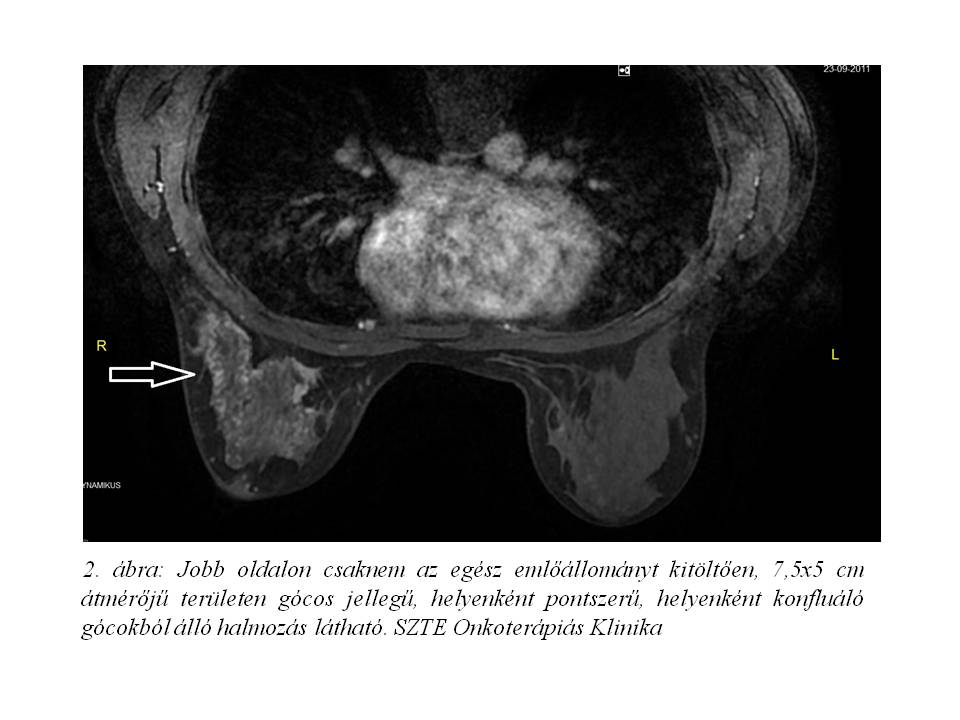

• Emlő MRI (1. ábra, 2. ábra): Jobb oldalon csaknem az egész emlőállományt kitöltően, 7,5x5 cm átmérőjű területen gócos jellegű, helyenként pontszerű, helyenként konfluáló gócokból álló halmozás látható. A jobb külső felső negyedben egy körülírtabb 25 mm átmérőjű halmozó terület látható. A belső felső negyedben egy 10 mm átmérőjű, szintén körülírtabb góc van. A jobb axillában egy 16 mm-es és több kisebb nyirokcsomó látható. Vélemény: A jobb emlő nagy részét infiltráló, a quadránshatárokon átterjedő gócos jellegű, a halmozás dinamikája alapján malignusnak tartható folyamat.